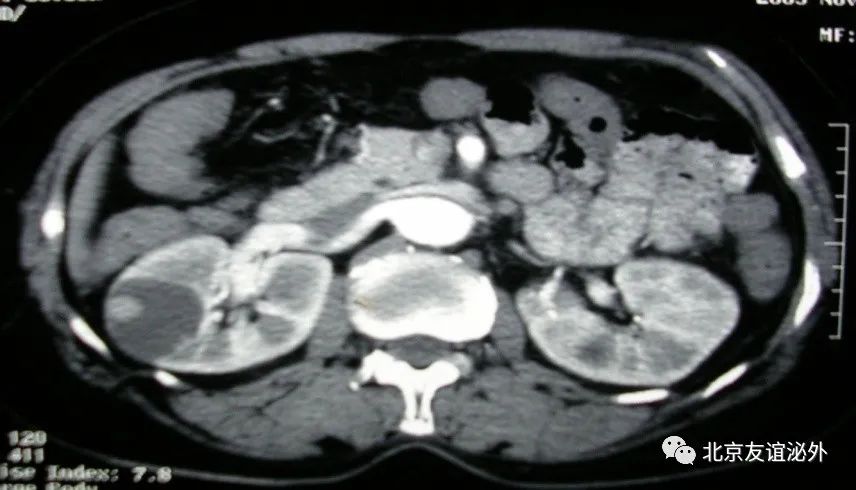

图2. Bosniak I级恶性囊肿(肾透明细胞癌),临床极为少见